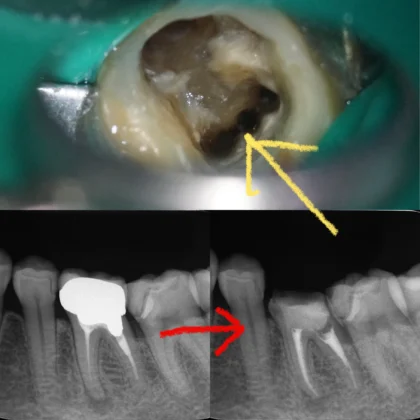

この黄色い矢印の所をMM根といって、下の奥歯で稀に見つかる、4番目根管です👀

下のレントゲンは術前と術後です。術前に治療できてなかった根管がしっかりと治療出来たので、一安心です😀